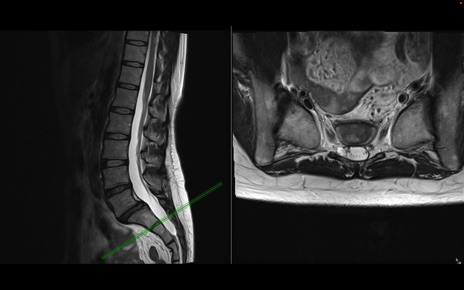

腰椎MRI

T2WI(横断像)

T2WI(矢状断像)